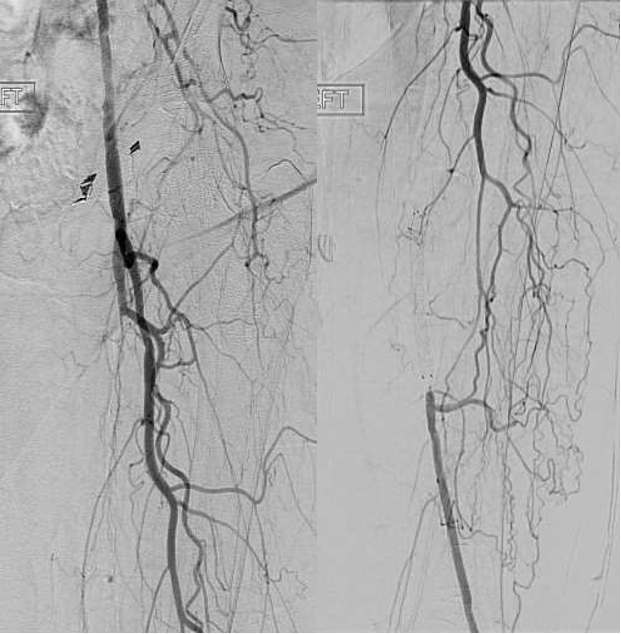

图:复杂股腘动脉病变CT